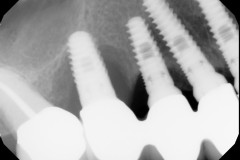

This mouth had recession on just one tooth with very little bone to support the tooth. The area needed support and thickness. The tissue was placed and the area now has thicker tissue to withstand the forces that the patient needs to place on it.

Click on a thumbnail to view the before and after photos.